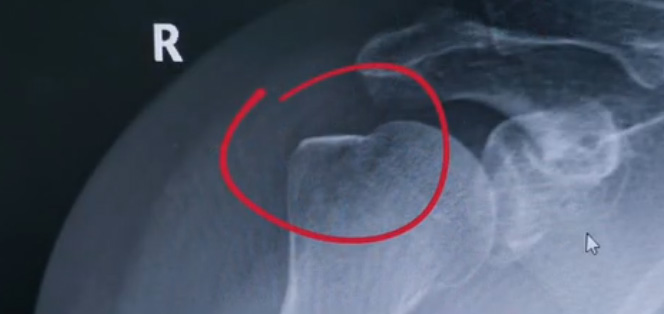

肩關節(jié)的X射線片子,看到?jīng)]有明顯的骨折,但是實際上已經(jīng)骨折了。那么是如何發(fā)現(xiàn)的呢?醫(yī)生對于做出疾病診斷的時候,會選擇什么樣的檢查方式。也更好的配合醫(yī)生,來解決問題。1米高的地方摔了下來,右側肩關節(jié)與地面相撞受傷了。當時的胳膊還能活動,疼痛感很明顯,但是在家觀察了一天,這個腫脹沒有明顯的加重。然而問題是什么呢?疼痛始終不能緩解,所以就需要到醫(yī)院檢查。醫(yī)生查看關節(jié)的受限也很明顯,尤其做外展這個動作的時候,幾乎沒辦法自行完成。肩關節(jié)內(nèi)的這個韌帶和肌腱可能還沒有發(fā)生嚴重的損傷。

首先做一個普通的X光檢查,看一看有沒有大的骨折或大的問題。結果是沒有發(fā)現(xiàn)太嚴重骨折損傷問題。結合病史,還是有點疑惑。因為疼的太厲害。x光檢查和他的疼痛之間不匹配,患者沒有骨頭的損傷,疼痛不至于達到這么嚴重的一個程度。是否有一種情況掩蓋住了病情。這也是X線檢查的通病。x光檢查它是一個二維的檢查,有可能患者肩關節(jié)啊發(fā)生了骨折。但是它的位置被前方或者側方的這個骨頭遮擋住了。不是立體的就沒辦法看到后方的情況。想要更加進一步的明確問題,判斷是否有骨頭的損害怎么辦?

進一步就是查CT,可以更全面的角度去判斷問題的所在。就會發(fā)現(xiàn)是否骨折可以看到確實存在著骨折,還好骨折不算嚴重??梢哉f是一個骨裂。這個肩關節(jié)與地面撞擊的時候,暴力沒有達到那么強。讓骨頭整個發(fā)生一個巨大的斷裂,而是造成了一個小的劈裂。適當?shù)倪M行一些抗炎止痛藥的使用。適當?shù)倪M行一些消腫治療,患者癥狀也就消失了。